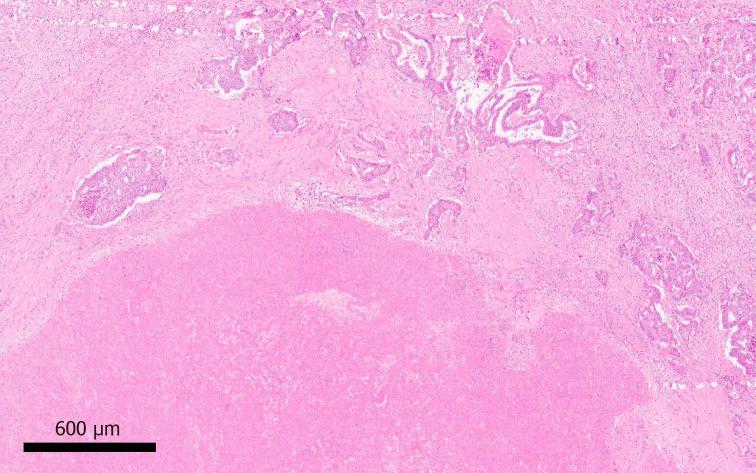

The liver is the commonest site of metastatic disease for patients with colorectal cancer, with at least 25% developing colorectal liver metastases (CRLM) during the course of their illness. The management of CRLM has evolved into a complex field requiring input from experienced members of a multi-disciplinary team involving radiology (cross sectional, nuclear medicine and interventional), Oncology, Liver surgery, Colorectal surgery, and Histopathology. Patient management is based on assessment of sophisticated clinical, radiological and biomarker information. Despite incomplete evidence in this very heterogeneous patient group, maximising resection of CRLM using all available techniques remains a key objective and provides the best chance of long-term survival and cure. To this end, liver resection is maximised by the use of downsizing chemotherapy, optimisation of liver remnant by portal vein embolization, associating liver partition and portal vein ligation for staged hepatectomy, and combining resection with ablation, in the context of improvements in the functional assessment of the future remnant liver. Liver resection may safely be carried out laparoscopically or open, and synchronously with, or before, colorectal surgery in selected patients. For unresectable patients, treatment options including systemic chemotherapy, targeted biological agents, intra-arterial infusion or bead delivered chemotherapy, tumour ablation, stereotactic radiotherapy, and selective internal radiotherapy contribute to improve survival and may convert initially unresectable patients to operability. Currently evolving areas include biomarker characterisation of tumours, the development of novel systemic agents targeting specific oncogenic pathways, and the potential re-emergence of radical surgical options such as liver transplantation.

肝脏是结直肠癌患者发生转移性疾病最常见的部位,至少25%的患者在病程中会出现结直肠癌肝转移(CRLM)。CRLM的管理已发展成为一个复杂的领域,需要多学科团队中有经验的成员参与,这些成员包括放射科(横断面、核医学和介入科)、肿瘤科、肝脏外科、结直肠外科和组织病理学。患者管理基于对复杂的临床、放射学和生物标志物信息的评估。尽管在这个非常异质性的患者群体中证据尚不充分,但使用所有可用技术最大限度地切除CRLM仍然是一个关键目标,并且提供了长期生存和治愈的最佳机会。为此,通过使用降期化疗、门静脉栓塞优化肝残余体积、联合肝脏分隔和门静脉结扎分期肝切除术以及在改善未来残余肝脏功能评估的背景下将切除与消融相结合,来最大限度地进行肝切除。肝切除可以安全地通过腹腔镜或开放手术进行,并且在选定的患者中可以与结直肠手术同步或在结直肠手术之前进行。对于不可切除的患者,包括全身化疗、靶向生物制剂、动脉内灌注或载药微球化疗、肿瘤消融、立体定向放疗和选择性内照射放疗在内的治疗选择有助于提高生存率,并且可能将最初不可切除的患者转变为可手术切除。目前正在发展的领域包括肿瘤的生物标志物特征化、针对特定致癌途径的新型全身药物的开发以及肝移植等根治性手术选择可能的重新出现。